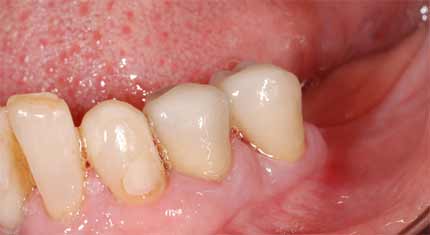

Qui viene mostrato un caso in cui la estrazione delle radici avrebbe avuto come conseguenza la perdita dell'osso già sottile e la conseguente impossibilità di inserire degli impianti dentali con tecnica standard.

Le foto mostrano il caso prima e dopo il recupero delle radici dentarie.

Si esegue un intervento chirurgico parodontale (allungamento di corona clinica) per adattare la gengiva alla radice recuperata.